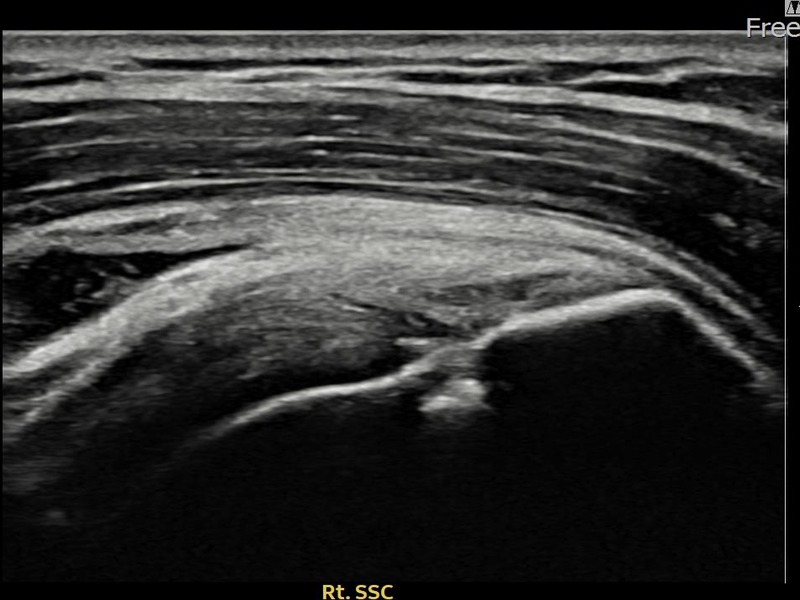

유ㅇㅇ님 · 우측 견갑하근건 관절면측 부분파열

우측 어깨 전방 통증과 팔 내회전 제한으로 내원하셨습니다. 초음파 검사에서 견갑하근건 관절면측 부분파열이 확인되었으며, 어깨인대 축소봉합술 후 힘줄 구조적 안정화가 이루어졌습니다.

유ㅇㅇ님 · 우측 견갑하근건 부분파열

우측 어깨 전방 통증과 팔 들어 올리기 어려움으로 내원하셨습니다. 초음파 검사에서 견갑하근건 부분파열이 확인되었으며, 어깨인대 축소봉합술 후 힘줄 연속성이 회복되고 어깨 기능이 정상화되었습니다.